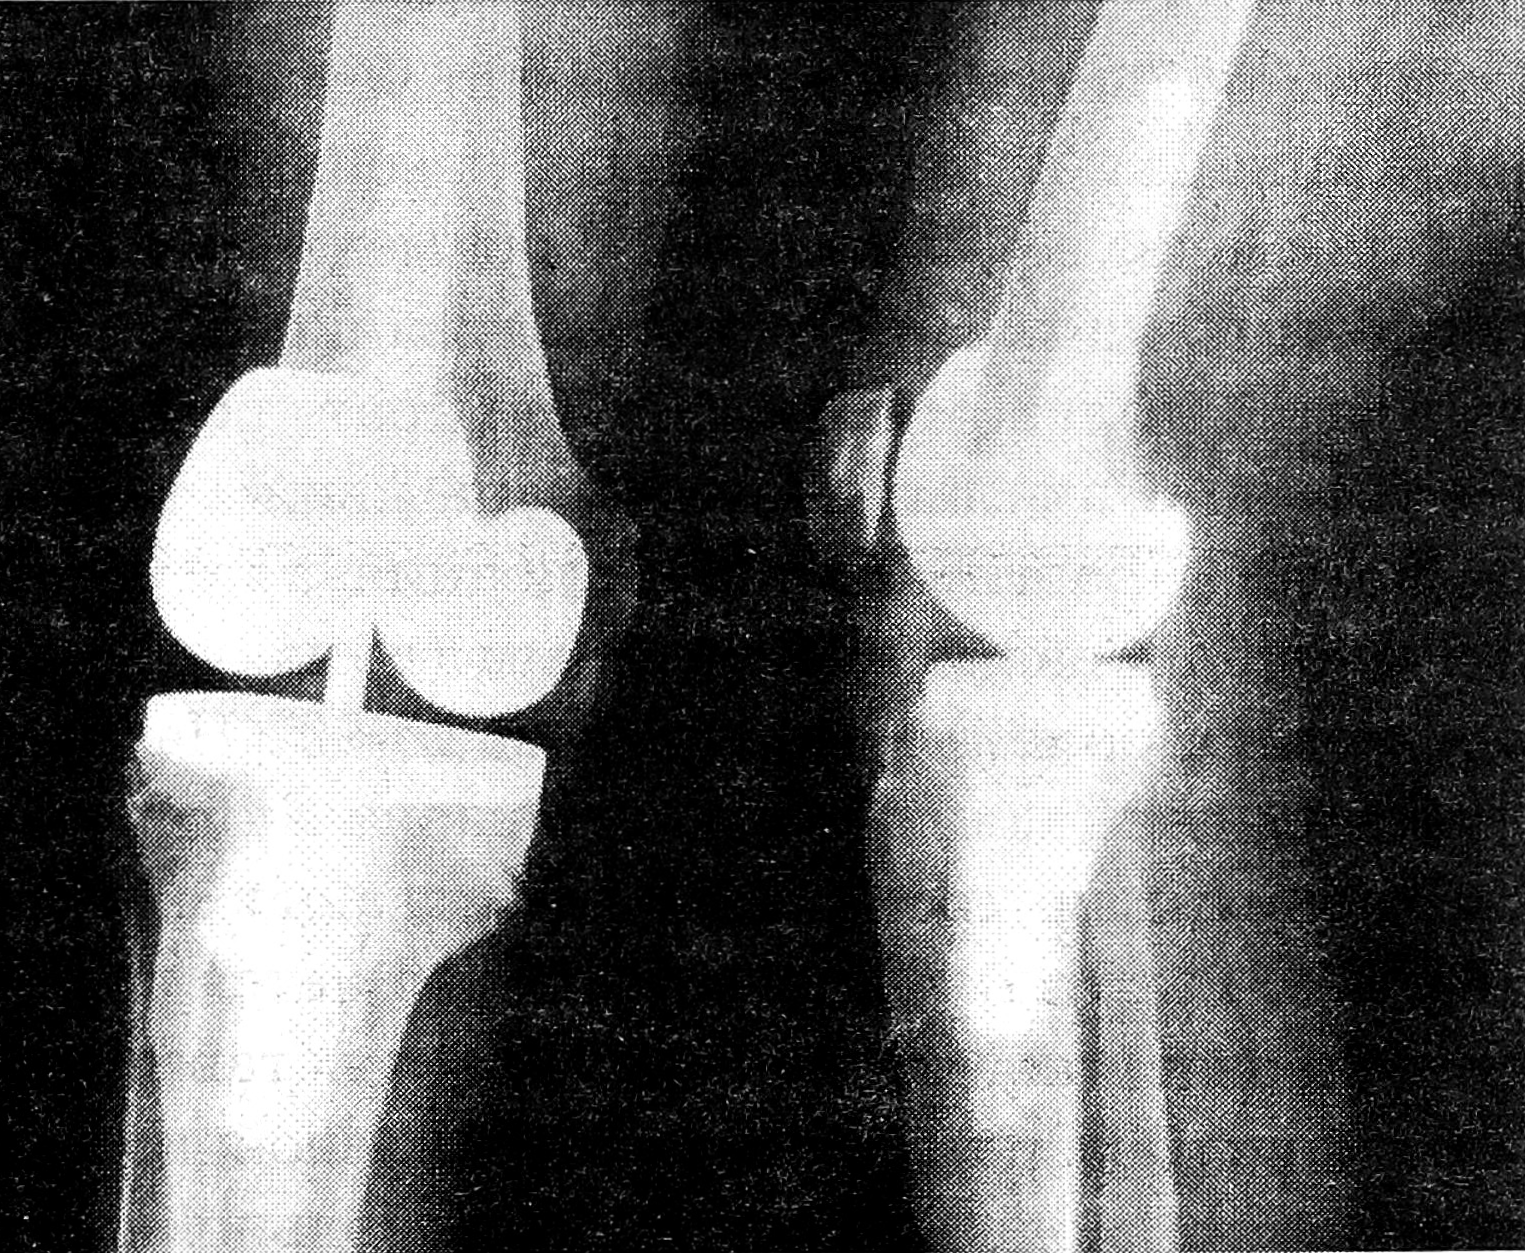

Больная Ш., 1918 года рождения, впервые обратилась в ЦИТО в 1990 г. с жалобами на боли в обоих коленных суставах, деформацию, нарушение опорности конечностей. Выявлены двусторонний гонартроз III стадии, контрактура обоих коленных суставов, варусная деформация (рис. 1, а). Больна в течение 30 лет. В 1988 г. произведена операция — лавсанопластика передней крестообразной и внутренней боковой связок правого коленного сустава. Боли в суставе продолжали беспокоить.

В 1991 г. в ЦИТО выполнено тотальное эндопротезирование левого коленного сустава протезом «ЕСКА medical» (рис. 1, б). Послеоперационный период протекал без осложнений, рана зажила первичным натяжением. Больная выписана домой через 3 нед после операции. При выписке болей в суставе нет, ось конечности восстановлена, контрактура в коленном суставе устранена, сгибание увеличилось до 90°.

В 1994 г. больная повторно госпитализирована в ЦИТО с жалобами на боли в правом коленном суставе. При осмотре определяются деформация сустава, варусное отклонение голени, контрактура под углом 170°, сгибание в суставе до 150°. В июне 1994 г. произведено тотальное эндопротезирование правого коленного сустава протезом «Intermedics- Orthopaedics», для крепления протеза применен костный цемент (рис. 2). Послеоперационное течение гладкое. Рана зажила первичным натяжением. Больная выписана из отделения через 3 нед после операции. При выписке болей в суставе нет, деформация и контрактура устранены, сгибание в обоих коленных суставах в пределах 180—90°. При осмотре через 6 мес жалоб не предъявляет, ходит без дополнительных средств опоры (рис. 1, в).

Рис. 1. Рентгенограммы левого коленного сустава больной Ш. (прямая и боковая проекции).

a — до эндопротезирования; б — непосредственно после тотального эндопротезирования протезом «ЕСКА medical»; в — через 3 года после эндопротезирования.

Рис. 2. Рентгенограммы правого коленного сустава той же больной Ш. после тотального эндопротезирования протезом «Intermedics-Orthopaedics» (прямая и боковая проекции).